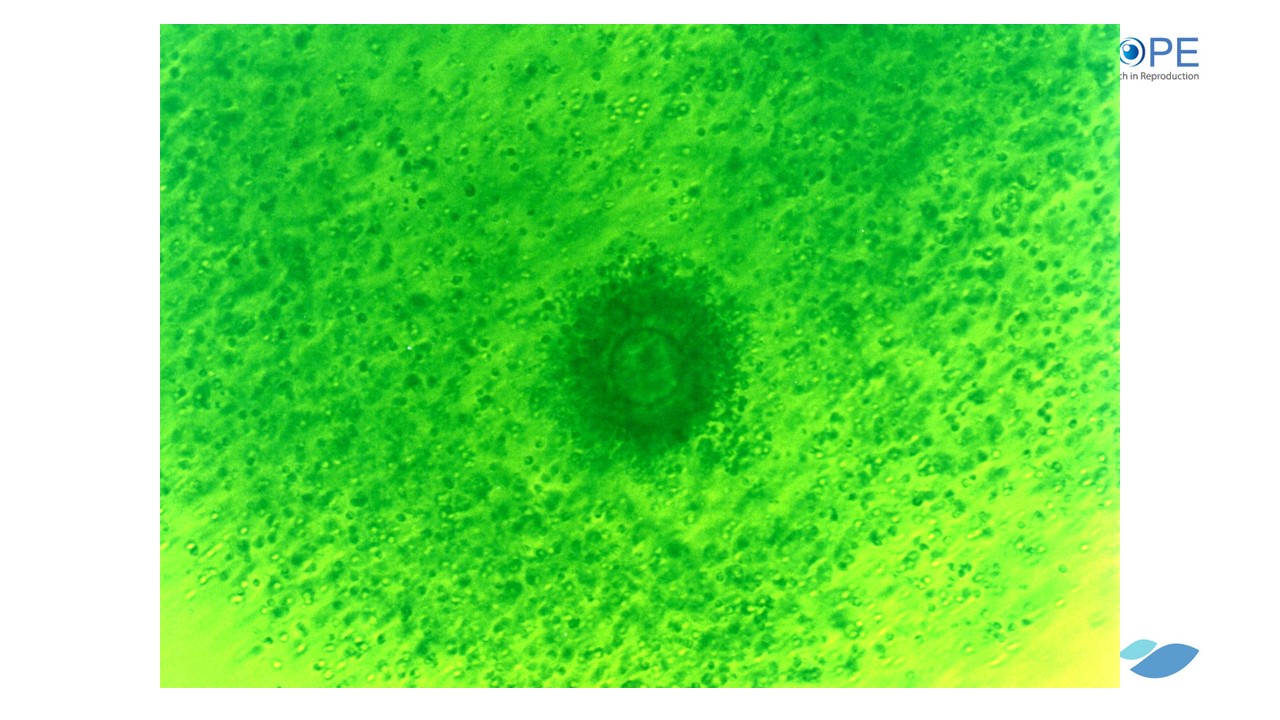

Thụ tinh ở người